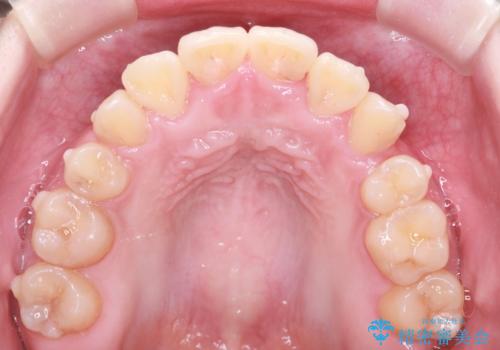

- 上下の前歯に激しい段差がある**重度の叢生(がたつき)**を主訴にご来院されました。精密検査の結果、歯をきれいに並べるためのスペースが圧倒的に不足していたため、上下左右の4番目の歯(第一小臼歯)を計4本抜歯する計画を立案しました。

本症例では、まず抜歯した大きなスペースを効率よく使い、歯の根元から大きく動かす必要があるため、初期段階にワイヤー矯正を採用。その後、細かな噛み合わせの調整や仕上げにインビザラインを使用する「ハイブリッドな矯正治療」で、期間の短縮と精度の高い仕上がりを目指しました。

ワイヤー矯正による先行治療: 最初のステージでは、ワイヤー装置を使用して抜歯したスペースへ歯を大きく移動させました。重度の叢生の場合、ワイヤーを用いることで歯のねじれや大きな移動をスピーディーに行うことができ、治療期間の短縮につながります。

治療の結果、重度のがたつきは跡形もなく解消され、抜歯したスペースもきれいに閉じました。ワイヤーによる「確実な移動」と、インビザラインによる「緻密な仕上げ」を組み合わせることで、審美性と機能性の両立を叶えた美しい歯並びを実現しました。